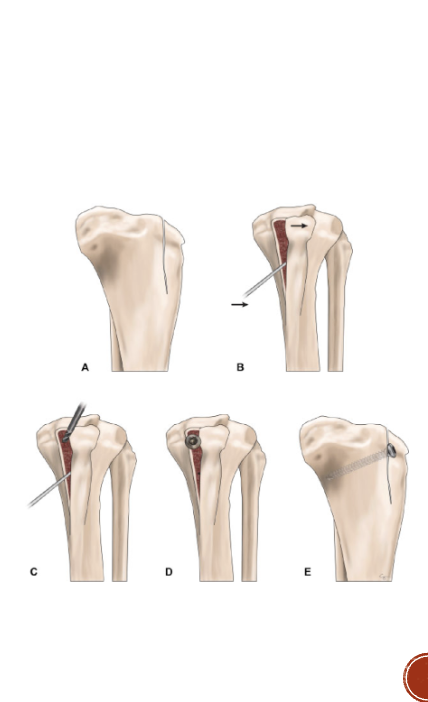

MLP surgical procedure

Lateral imbrication

Trochlear modification

Tibial crest (tuberosity) transportation